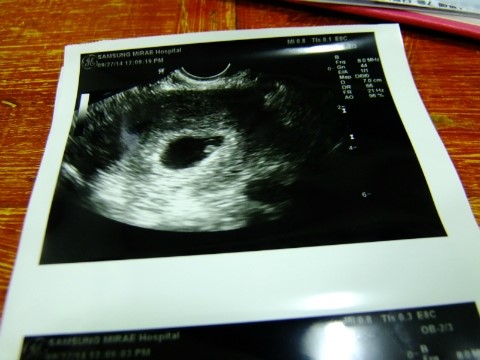

[6주 4일] 첫 초음파 확인! 뚝심아 안녕 :)

2014, 09, 27 드디어 기다리고 기다리고 기다리고 기다...